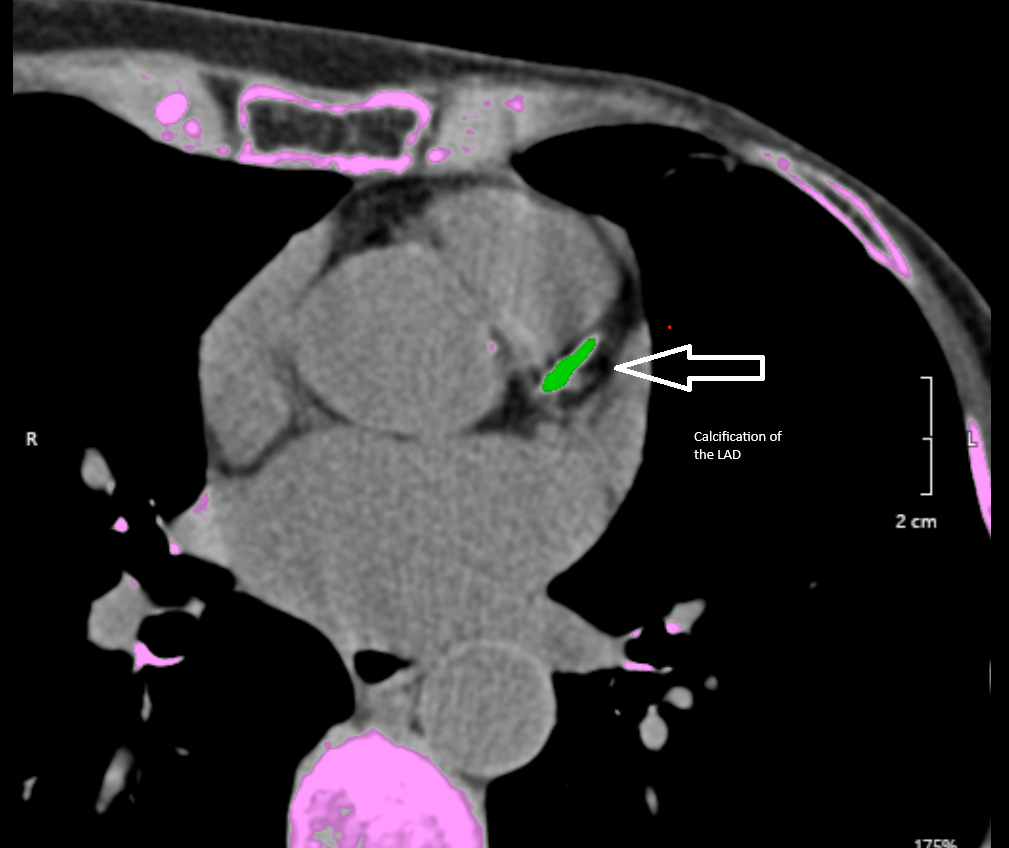

Cardiac calcium scans are painless and performed at our ImageCare locations (see specific locations below). This examination utilizes a computed tomography machine, more commonly known as a CT or CAT scan, to generate multiple cross-sectional images. Calcium scoring using cardiac CT is a non-invasive method for evaluating the coronary artery walls for calcified plaque buildup.

The coronary arteries are the vessels that supply oxygen-containing blood to the heart muscle. Calcified plaque results when there is a buildup of fat and other substances under the inner layer of the artery. The coronary arteries typically do not contain calcium. The presence of calcium in the coronary arteries indicates coronary artery disease and is an indicator of heart disease. Because calcium is a marker of the disease, calcium levels are a helpful tool for your provider, and the results are reported as a cardiac score.